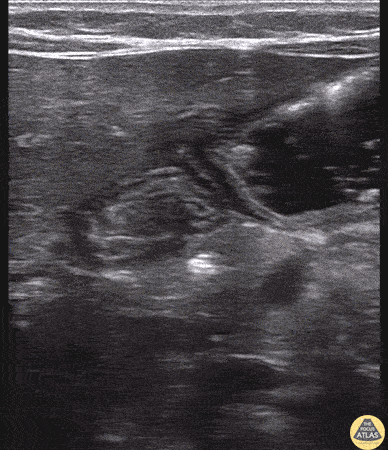

4-week-old with vomiting, projectile according to parents. Infant tolerating formula feed well in ED. On exam well-appearing infant with soft abdomen and no masses to palpation. POCUS reveals a normal appearing pylorus. Thickness of muscle < 3mm and length < 14mm. The patient was fed just before exam thus fluid can be seen swirling in the stomach. This can aid in visualization of the pylorus. Sometimes fluid can be seen passing through the pylorus. Dr. Sathya Subramaniam, Pediatric EM Fellow - Kings County/SUNY Downstate